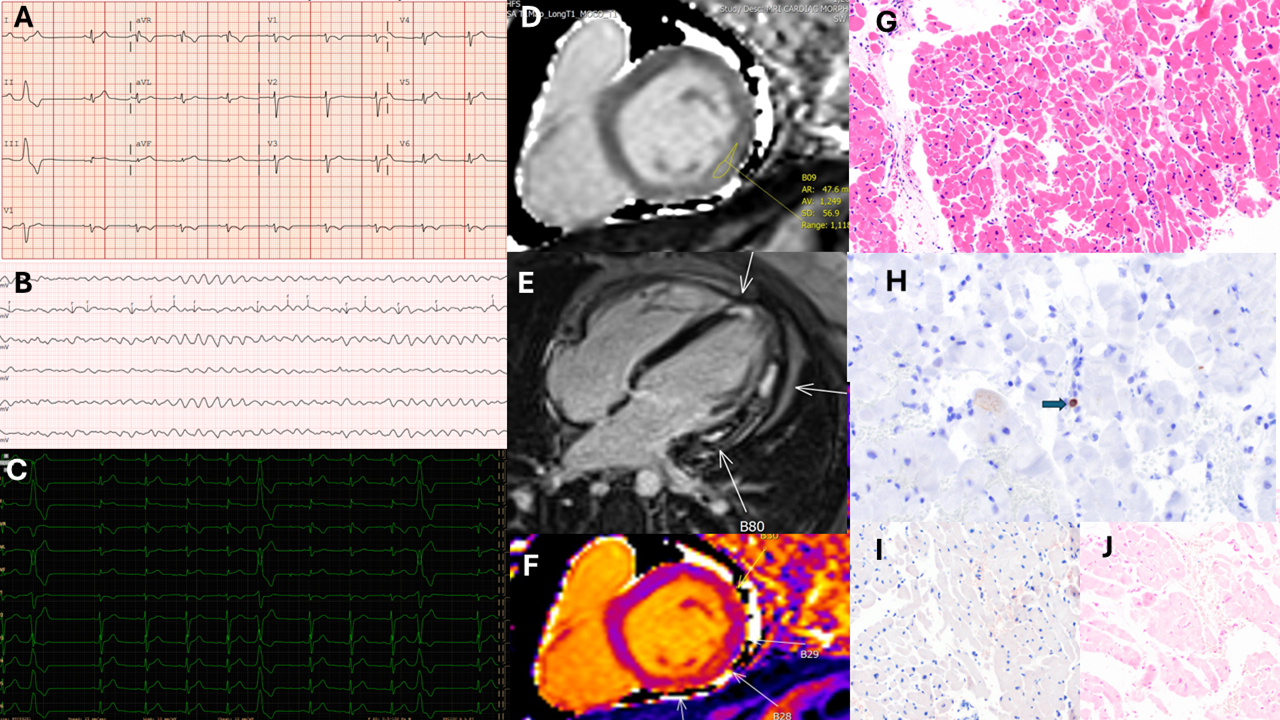

Abstract Body (Do not enter title and authors here): Case Description: A 27-year-old male with unremarkable past medical history presented with non-bloody diarrhea and nausea and vomiting of 5 days duration. While in the emergency department, he reported substernal non-pleuritic and non-radiating chest pain. On cardiac monitor he was noted to have frequent premature ventricular complexes (>5%) arising with superior portion of left ventricle and ECG showed new ST elevation in lead II and aVF. Emergent coronary angiogram showed no coronary artery stenosis or vasospasm. Post cardiac catheterization he had Torsade de Pointes requiring defibrillation. Electrolytes were in normal range, but elevated cardiac biomarkers were elevated. Right heart catheterization showed elevated filling pressures with normal cardiac output and index, 5.6 L/min, and 2.3 L/in/m2, respectively. Endomyocardial biopsy was negative for lymphocytic, giant cell, or granulomatous inflammation. A Prussian blue iron stain for hemochromatosis and Congo red for amyloidosis were negative. Echocardiogram showed no structural heart disease with normal right and left ventricular size but mildly decreased function (LVEF 40-45%). Cardiac MRI showed large areas of left ventricular linear subepicardial gadolinium enhancement not in a coronary territory associated with pericarditis. He had leukocytosis and an infectious work up including gastrointestinal panel was positive for Astrovirus. He was treated with beta blockers, angiotensin receptor blocker and high dose steroids. No recurrent ventricular arrythmia noted in one week and premature ventricular complex burden decreased. He was scheduled for subcutaneous defibrillator and follow up with cardiac MRI.

Discussion: Astrovirus causes gastroenteritis in about 2-5% of children and rarely adults. Murine models of Astrovirus infection showed its cardiovascular tropism. Here we present the first case of astrovirus-myopericarditis. Ventricular arrhythmias may occur due to electrolyte abnormalities that are commonly seen in a gastroenteritis as well as direct cardiac injury and inflammation caused by viral replication or bystander immune response. The localization of premature ventricular complexes shows possible origin from superior portion of left ventricle with active inflammation noted in T2 weighted cardiac MRI. Electrical instability requiring defibrillation placed our case in stage D myopericarditis.